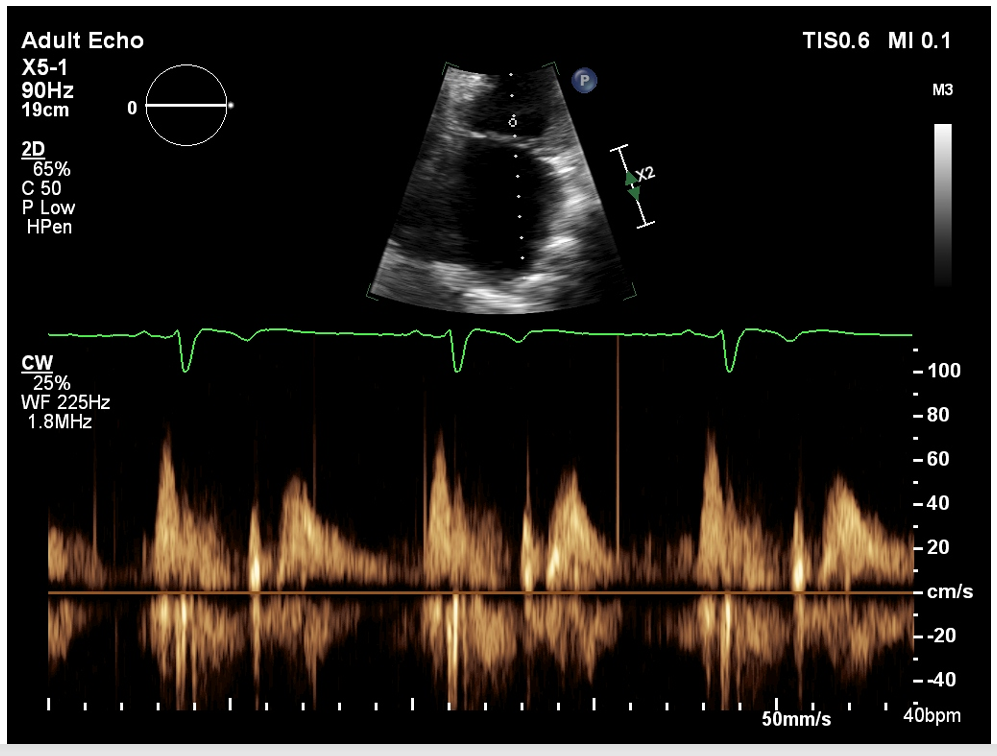

what measurement would this be

trace this measure when you get a really nice envelope, this is she MVR PISA method and measure MVR VTI (the jet is u-shaped)

what is this measurement for

This measuring above the baseline for stenosis, this is our MV VTI

you want to Trace the E and A, a normal MV mean gradient is going to be less than five (if we see a very heavy calcified vale that is not opening well the CW is going to assessing for)